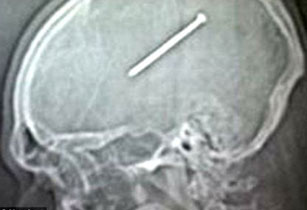

9 սմ-անոց մեխը 3 օր մնացել է ամերիկացու գանգի մեջ

ԱՄՆ-ի Իլինոյս նահանգի բնակիչ Դանթե Աութուլոն շինարարական աշխատանքի ժամանակ մեխ կրակող ատրճանակով պատահմամբ կրակել է դեմքի ուղղությամբ, և մոտ 9 սմ-անոց մեխը մխրճվել է նրա գանգի մեջ։ Այս մասին գրում է «All Voices» լրատվական գործակալությունը։

Զարմանալին այն է, որ Աութուլոն 3 օր բուժօգնության չի դիմել՝ պնդելով, թե լուրջ ցավեր չի էլ զգացել.

«Շատերի համար զարմանալի է, բայց ես իսկապես լուրջ ցավեր չեմ ունեցել։ Մի քիչ գլուխս էր պտտվում, այլապես բժշկի չէի դիմի»,-ասել է Դանթեն։

Բժիշկները մեխը հեռացրել են, բայց մինչև հիմա ապշած են՝ ինչպես կարելի է նման վիճակում երեք գիշեր գլուխը հանգիստ դնել բարձին։